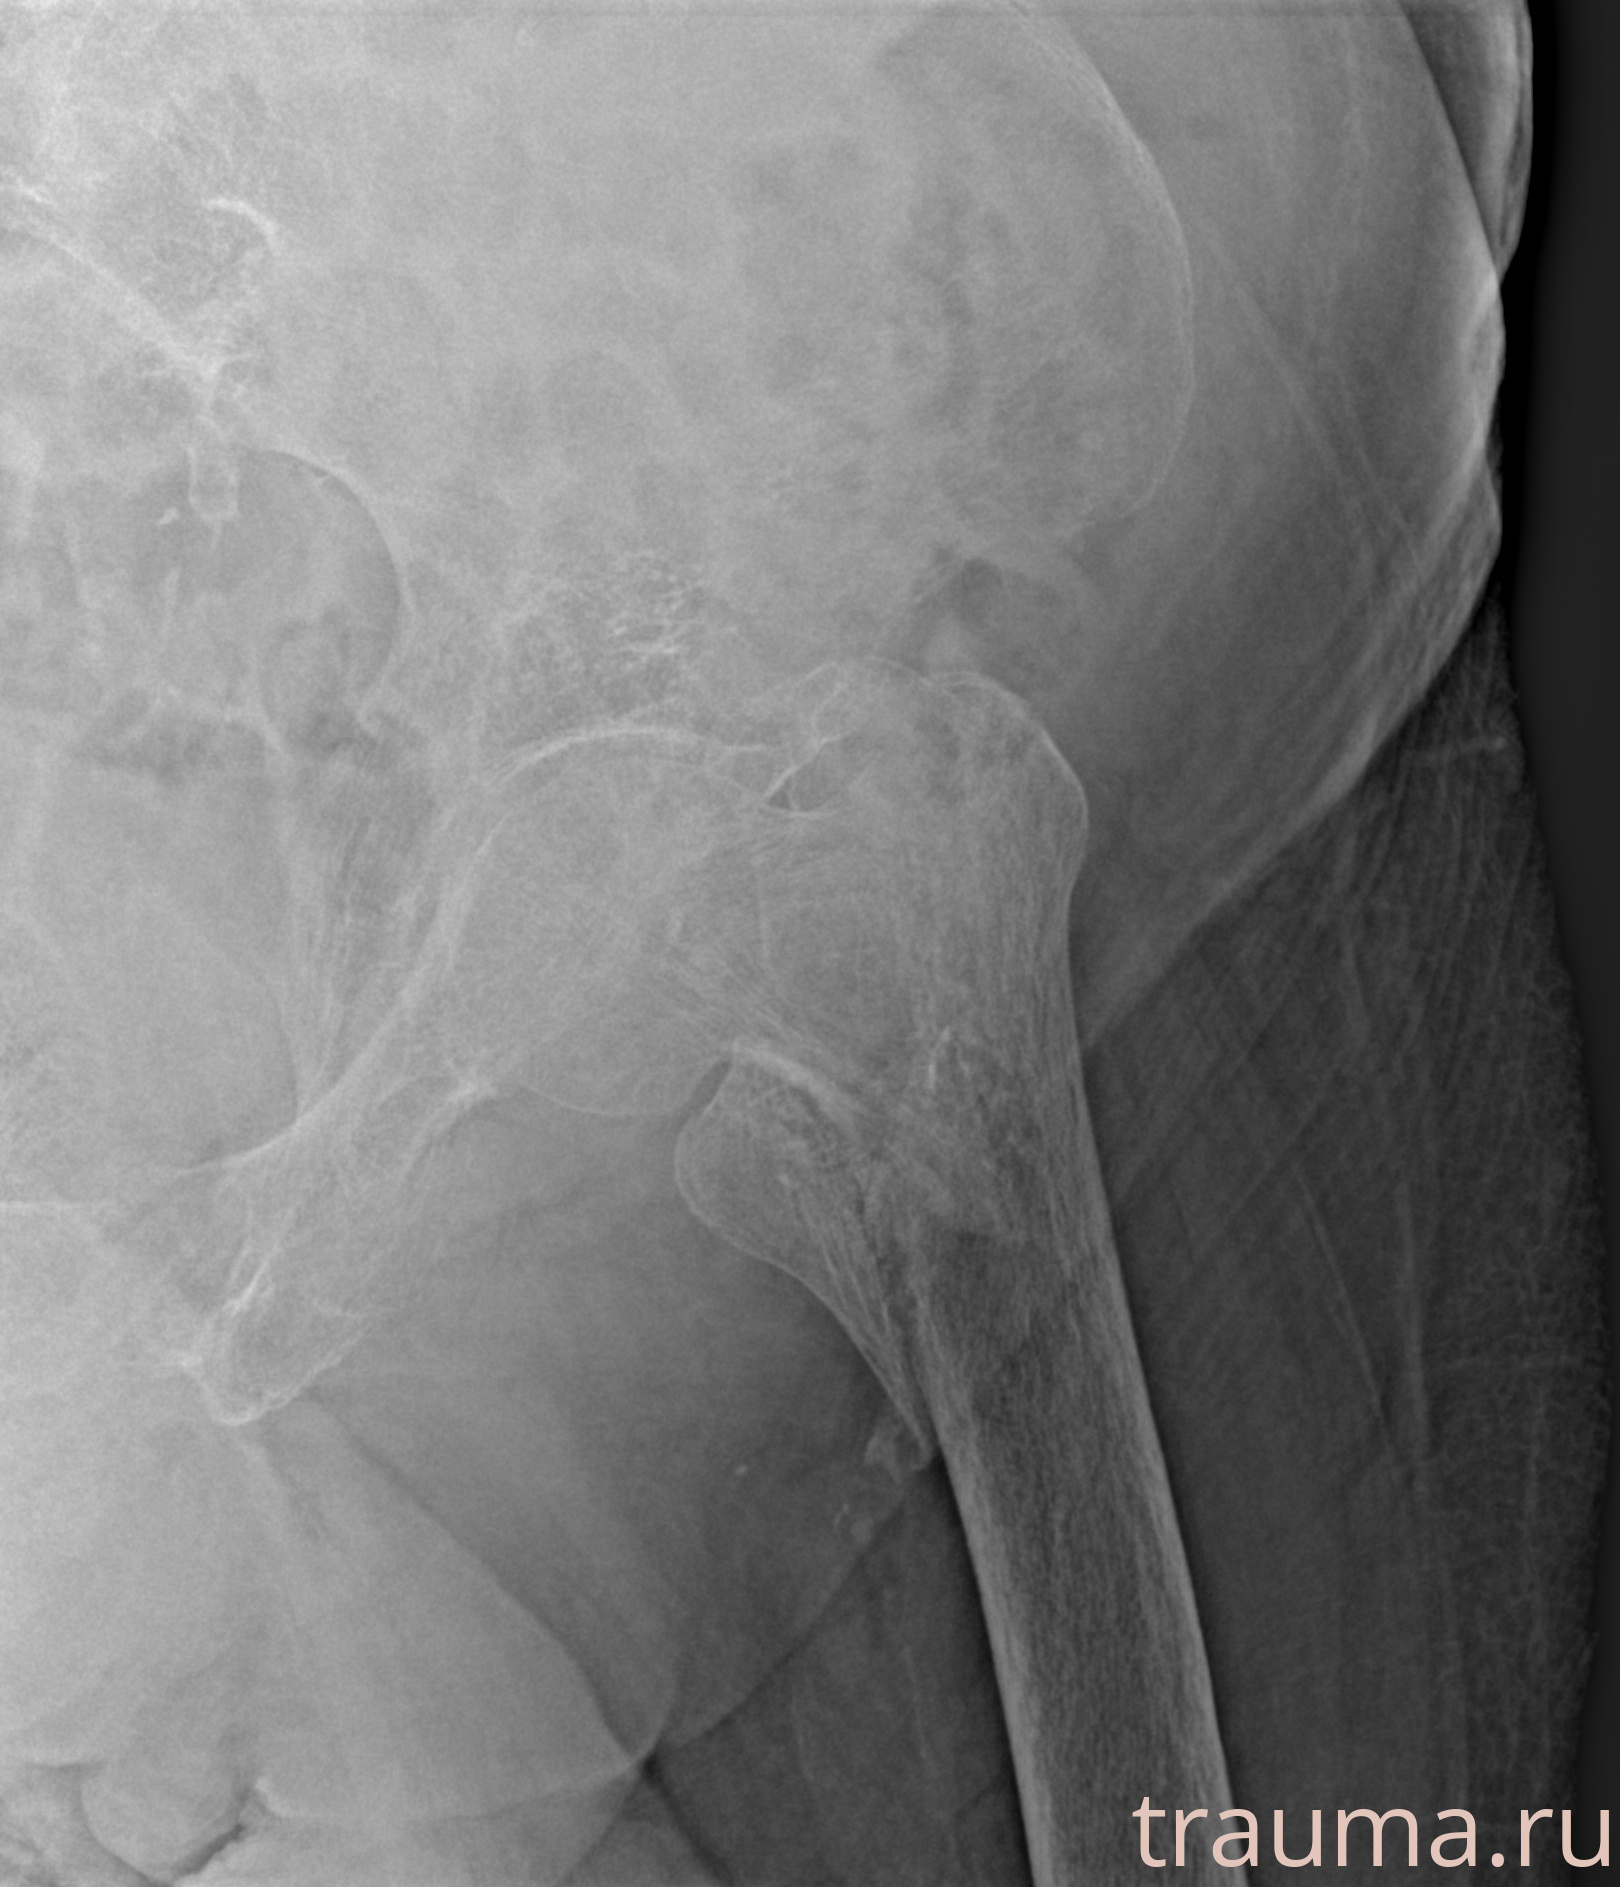

Первая помощь при переломе шейки бедра

Рентген на дому: по вашему адресу приезжает врач-рентгенолог, травматолог-ортопед с мобильным рентгеновским аппаратом, проводит диагностику травмы или заболевания, делает необходимые рентгенограммы, дает рекомендации по дальнейшему лечению. Получить качественные снимки в домашних условиях возможно благодаря уникальной методике, разработанной МосРентген Центром для института  Склифосовского